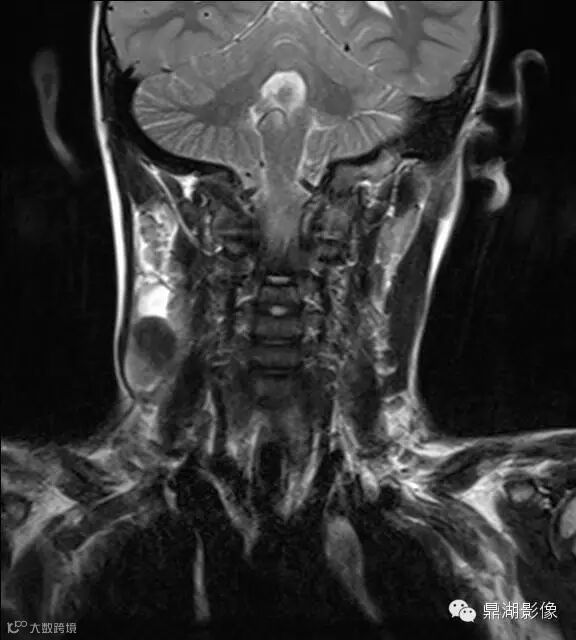

上海儿童医院韩燕乔教授诊断:考虑淋巴结炎 ,可见杯状分层,液液平

颌面部淋巴结炎是临床较常见的一种疾病,尤其是小孩发病率更高。经常发生在颌下及颏下,有时也发生在耳后,面部和颈侧。颌面部的淋巴结炎大多是以下原因引起感染。上呼吸道感染,如扁桃体炎、咽炎、鼻炎、鼻窦炎等;口腔感染,如牙龈炎、牙周炎、口腔溃疡、冠周炎等;皮肤损伤与感染,如头面部皮肤化脓性伤口、湿疹感染、疖肿等。以上各种感染的细菌均可以随着淋巴液的循环,流经颌面部的相应淋巴结,使相应部位的淋巴结遭受细菌的侵犯,引起淋巴结的炎症。

神经源性肿瘤:肿块较大,信号常不均,有人认为肿瘤位于屈肌的区域或伴有肌肉萎缩强烈提示神经源性肿瘤。

淋巴结核:多融合成团,呈花环状,边缘强化,淋巴结内见到斑点状钙化有助结核的诊断。

猫抓病性淋巴结炎:不少医生诊断为猫爪病,该病确实很接近。均为炎性改变,脓肿、坏死形成时,虽呈边缘强化特点,但多个淋巴结间界限清楚,无融合改变,内也无斑点状钙化。